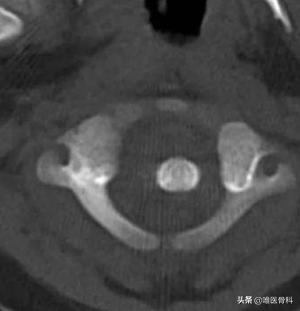

影像检查方面,我们多依靠颈椎X线侧位片、颈椎X线张口位片及CT检查明确。

如果颈椎侧位片显示齿状突与寰椎前结节之间距离>5mm,或张口位片显示枢椎与寰椎侧块间距离不对称,寰齿间距>3mm,寰底线中点垂线偏离齿状突平行线>1mm,即可诊断为寰枢关节半脱位。当然颈椎CT更能直观显示。